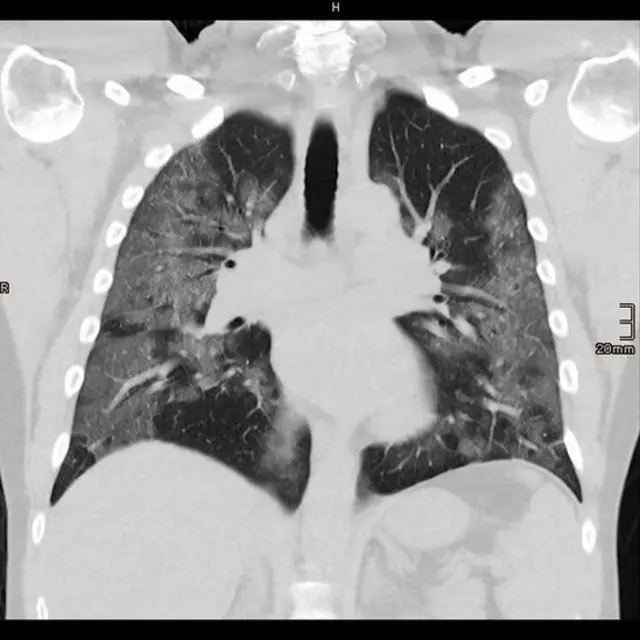

Le professeur Chris Brightling, de l'université de Leicester et chercheur en chef du projet PHOSP-Covid qui suit le rétablissement des personnes, pense que les personnes qui ont développé une pneumonie peuvent avoir plus de problèmes en raison des dommages causés aux poumons.

Crédit photo, HOSPITAL BETHANIEN MOERS/THOMAS VOSHAAR/Reuters

L'infection peut également modifier le fonctionnement des organes de l'homme. Cela est particulièrement évident dans le cas des poumons, s'ils présentent des cicatrices - des problèmes à long terme ont été observés après une infection par le Sars ou le Mers, qui sont tous deux des types de coronavirus.